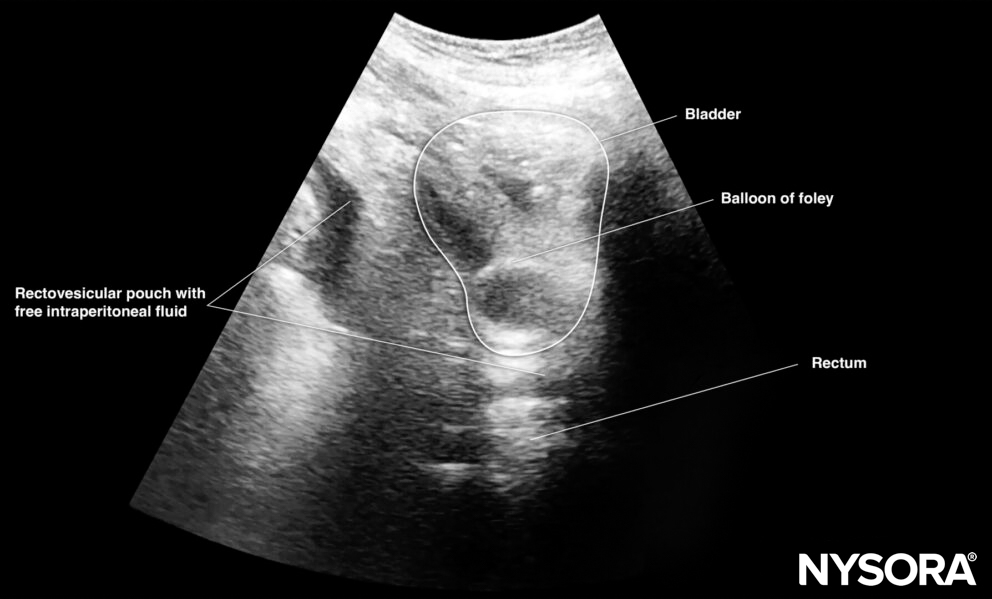

Sonoanatomy of interest in males:

Transverse view of the male pelvis with free fluid in the rectovesical pouch after Foley catheter insertion.

Pelvic free fluid collects behind the bladder or the area lateral to the bladder (rectovesical pouch in men and the rectouterine pouch or pouch of Douglas in women).

Sagittal section through the pelvis with free fluid in the rectovesical pouch in men and the rectouterine pouch (pouch of Douglas) in women.

- In men, the seminal vesicles may be mistaken for free fluid. However, the vesicles are usually more triangular in shape and symmetrically spaced from the midline in the transverse view.

- Adjust the gain to atone for the acoustic enhancement of the bladder, which makes it more difficult to observe hypoechoic free fluid posterior to the bladder.